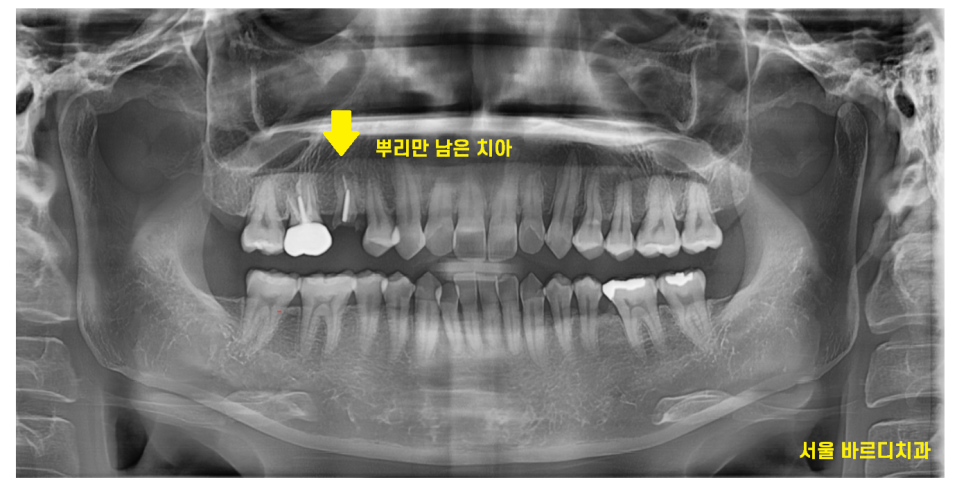

23.11.30

뿌리만 남은 치아입니다.

이정도로 부러졌으면 뽑고 임플란트를 해야하는데요.

24.04.30

환자분이 강동구 임플란트 수술을 결심하고

X-RAY를 촬영

그제서야 아...

왜 그동안 치과를 몇군데씩 다니셨나

이해가 되더라고요.

깨끗했습니다.